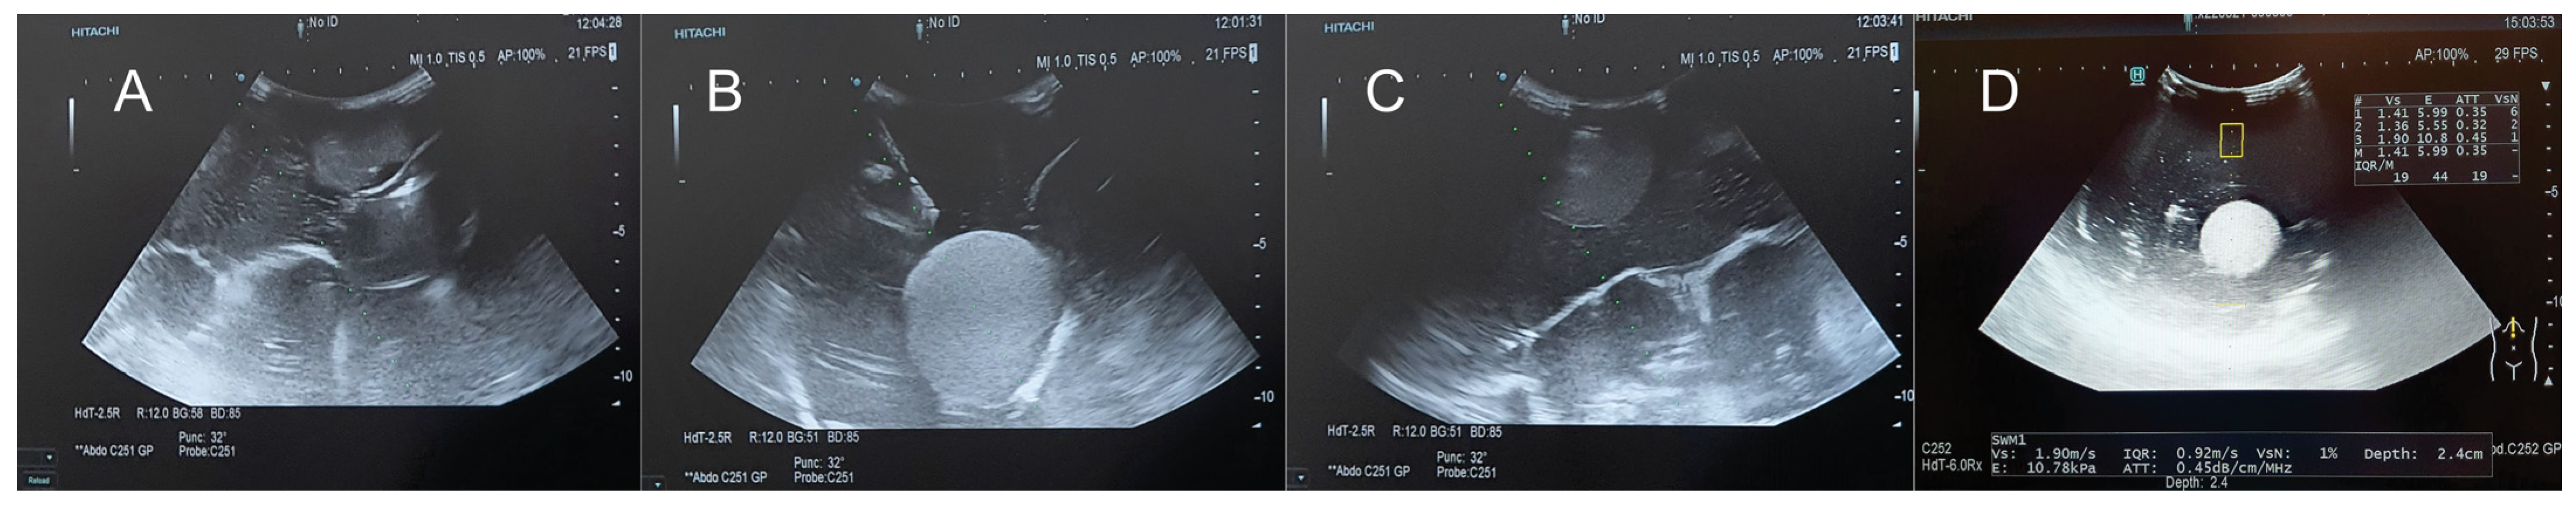

| Ultrasound | ![]() | ![]() | ![]() |